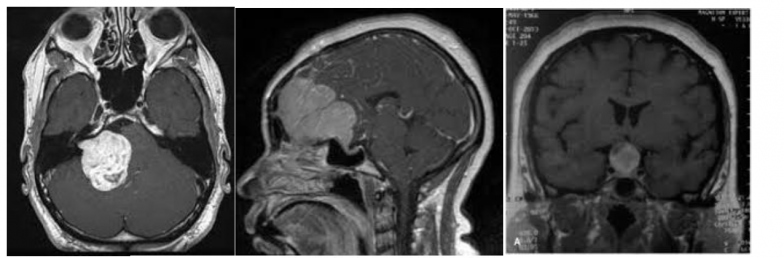

La neurocirugía craneal es una subespecialidad altamente compleja enfocada en el tratamiento de patologías intracraneales, incluyendo tumores cerebrales, traumatismos, malformaciones vasculares y alteraciones estructurales del sistema nervioso central.

Cada procedimiento requiere una planificación meticulosa basada en estudios de imagen avanzados, con el objetivo de intervenir de manera precisa y segura, minimizando riesgos y preservando la función neurológica del paciente.